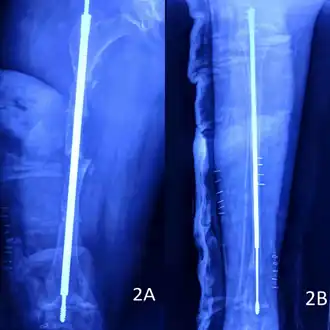

Rodding

Metal rods can be surgically inserted in the long bones to improve strength, a procedure developed by Harold A. Sofield when he was Chief of Staff at Chicago's Shriners Hospitals for Children, a hospital that offers orthopedic care and surgery to children regardless of their family's ability to pay.[115] Large numbers of children with OI came to Shriners, and Sofield experimented with various methods to strengthen their bones.[116] In 1959, with Edward A. Millar [sic], Sofield wrote a seminal article describing a three-part surgery that seemed radical at the time: precisely breaking the bones ("fragmentation"), putting the resulting bone fragments in a straight line ("realignment"), then placing metal rods into the intramedullary canals of the long bones to stabilize and strengthen them ("rod fixation").[117] His treatment proved useful for increasing the mobility of people with OI, and it has been adopted throughout the world—it became standard surgical treatment for severe OI by 1979, in which year David Sillence found that ≈2⁄3 of the patients he surveyed with OI type III had undergone at least one rodding surgery.[42]: 108

Rodding surgery is often done with the hope that it will offer a path to ambulation, walking, to patients with moderate or severe OI. A 2020 review in The Journal of Bone and Joint Surgery (JB&JS) found it remains broadly popular: ≈2⁄3 of people with OI types III and IV (severe OI) have undergone some form of rodding surgery in their lives, at a mean age of 4+1⁄10 and 7+1⁄2 years respectively;[25]: Table I one possible explanation for a tendency towards earlier intervention in type III is that one half of affected children could not walk at all without the surgery, as their limbs were more bowed, so surgery was sought sooner.[25]

In those with type III OI who had undergone rodding surgery, 79.5% had the femurs and tibias of both legs rodded.[25]: Table I The most common form of rods used are intramedullary (IM) rods, some of which, such as the Fassier–Duval IM rod, are telescoping, meaning that they are designed to grow as the child grows, in an attempt to avoid the necessity of revision surgeries.[118] Telescoping IM rods are widely used,[119] and the common Fassier–Duval IM rod is designed to be used to rod the femur, tibia, and humerus.[120]: 1 The surgery involves breaking the long bones in between one and three (or more)[119]: Figure 4 places, then fixing the rod alongside the bone to keep it straight.[120]: 11

While telescoping IM rods are intended to grow along with both the femur and tibia in developing children; surgeons have a preference to use non-telescoping IM rods, such as Rush rods, in the tibia, which grows less comparatively—the JB&JS review found that while 69.7% of femurs were treated with telescoping IM rods, only 36.9% of tibiae were.[25]: Table IV